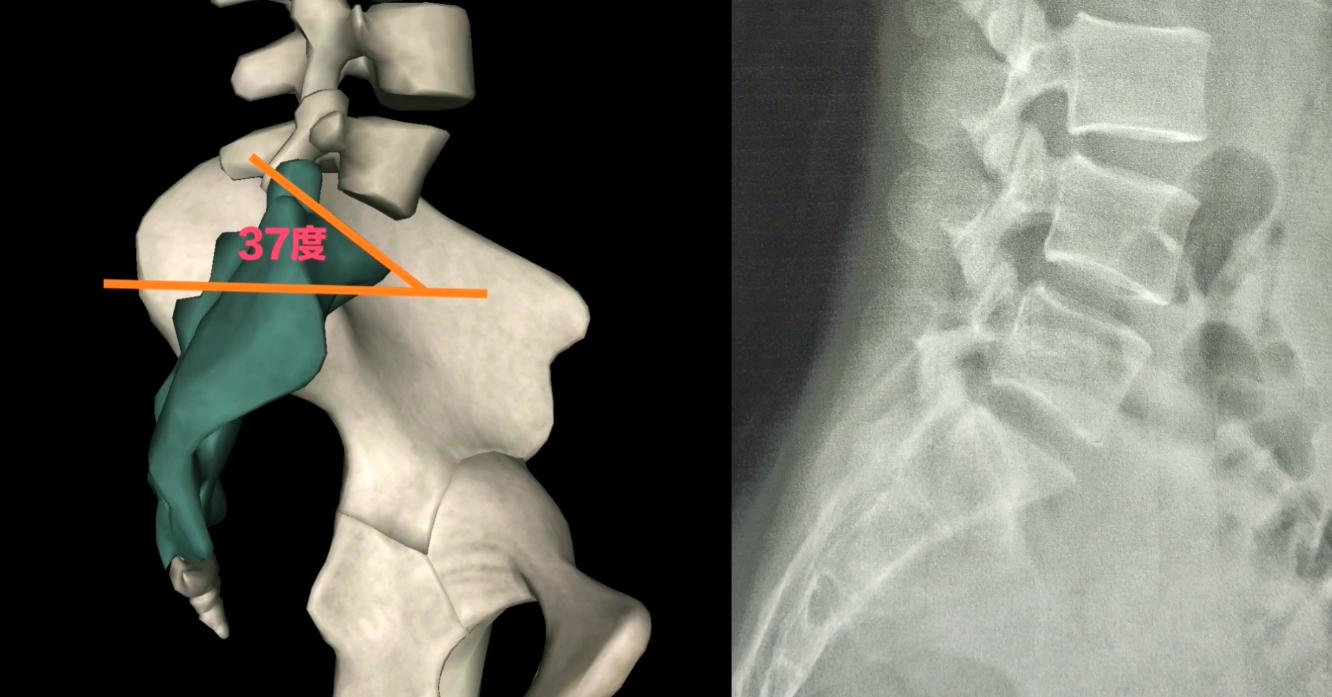

我们先来学习判读骶骨的上下偏位,

首先确认片子站立位拍摄,从腰椎的侧位片子去观察,

骶骨的角度参考标准正常是三十七度,

大于三十七度,就属于骶骨向上(点头),

小于三十七度属于骶骨向下(仰头),

从侧位片骶骨的上关节面前后画两个点,然后做连线,再以地表水平线做延长,相交之后产生的角度就是骶骨角,测量下角度是大于37,还是小于37,来确定骶骨是向上还是向下了